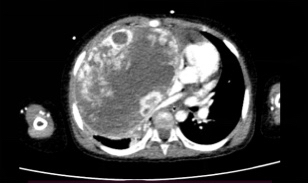

今年3月23日,3岁女孩玲玲(化名)因“咳嗽、喘息、气促”到华西第二医院就诊,本以为只是普通的内科疾病,却没想到因此发现了巨大肿瘤。胸部CT发现玲玲右侧胸腔内巨大软组织团块影,右心缘明显受压变形、右下肺野被动型压缩不张。玲玲在华西第二医院行“右侧胸腔肿瘤穿刺活检术”,病理结果显示:右侧胸腔活检形态示肿瘤浸润。

因肿瘤巨大占位导致玲玲气管下段、左右主支气管及右肺叶、段支气管明显狭窄,右肺外压性不张,玲玲需要经鼻高流量氧气辅助通气,才可以维持氧饱和度,在进行化疗后,肿瘤没有明显缩小,情况十分危急。